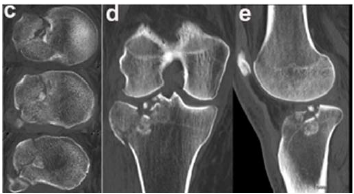

O exame apresentado indica o envolvimento do platô tibial

Um paciente de 39 anos de idade, vítima de queda de bicicleta, sofreu trauma no joelho direito. Foi levado ao pronto-socorro do hospital mais próximo, onde foram realizadas as radiografias apresentadas.

O exame de imagem mais apropriado para o estudo do caso é

Geralmente, o mecanismo de trauma dessas fraturas envolve